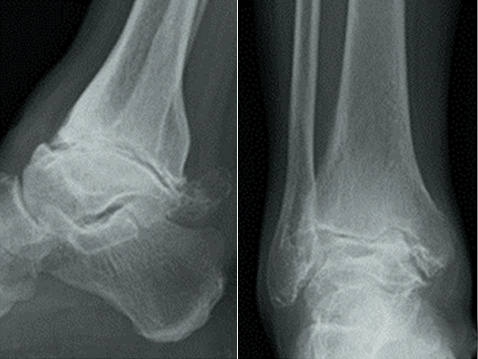

创伤性踝关节骨性关节炎前侧锁定钢板内固定踝关节融合手术前后X线片

1、前侧入路

前侧入路是以踝关节间隙为中心作前方纵形切口,逐层切开,沿肌腱间隙进入;切开关节囊,显露胫距关节,去除软骨及软骨下骨,将前侧钢板置于踝关节前方。